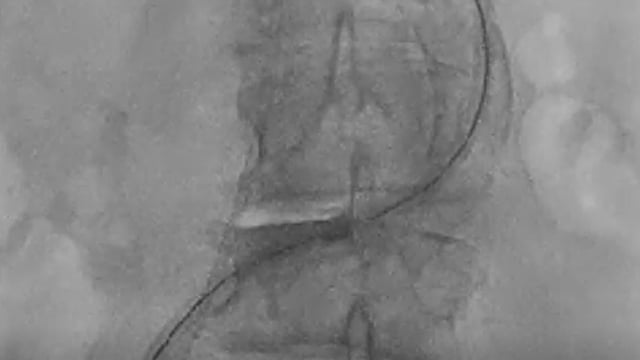

Severe MR in a high-risk patient with a suboptimal anatomy for M-TEER: what other options can we find?

Multimodality imaging reveals fibro-calcific leaflet disease, restricted motion, and a short posterior leaflet, making him a suboptimal candidate for M-TEER and prompting consideration of transcatheter mitral valve replacement. How would you treat?